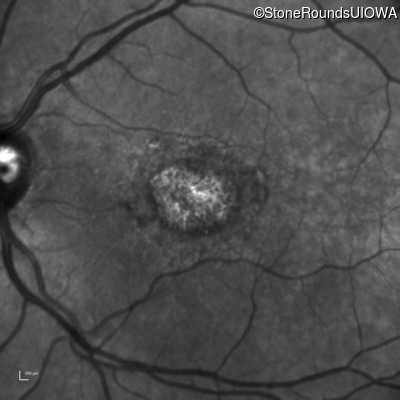

Blue Autofluorescence - Right - 20/125 -1

Exemplar